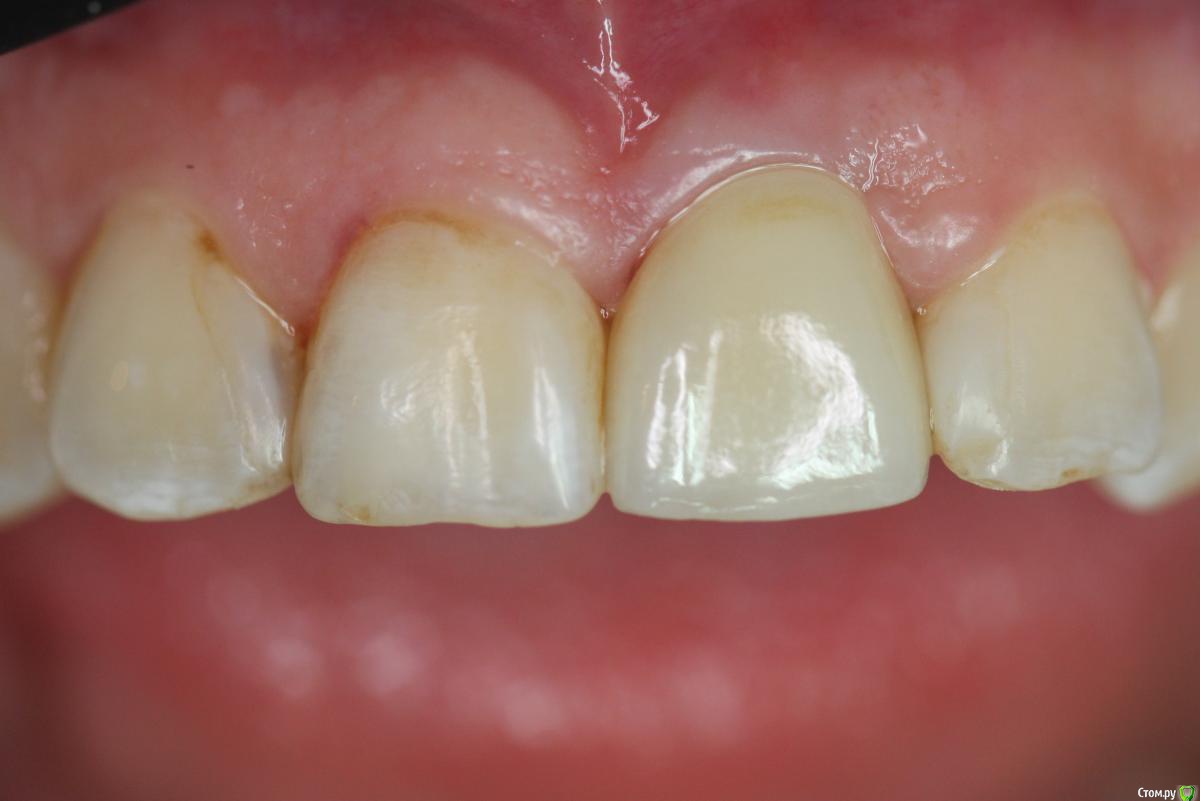

Zorrro Опубликовано 28 февраля, 2016 Поделиться Опубликовано 28 февраля, 2016 Пациента прислали на консультацию с кт. Огромная квк,ожидаемая трещина,локально гиперемия,подвижность коронки.Назначили аб терапию и записались на операцию через 2 дня.К сожалению нет фотодокументации с первой консультацией.Альтернативой немедленной нагрузки с костной и мягкотканной пластикой,были отсроченные костные блоки,с двухэтапным протоколом имплантации и тд и тп.С вероятным коллапсом мягких тканей,турбомобилизацией и прочими неприятными сопутствующими манипуляциями растянутыми по времени,а самое главное без ясного и прогнозируемого результата…короче решили рискнуть. Ссылка на комментарий

Zorrro Опубликовано 29 февраля, 2016 Автор Поделиться Опубликовано 29 февраля, 2016 (изменено) Через два дня пациент меня неприятно удивил.И ,безусловно,правильно было бы отменить операцию и ограничиться удалением,но… Вот такой был сюрприз под носом с нечищенными зубами.Обговорив риски,перекрестившись начали.Во время операции фото не делал.Слизистая в проекции 21 была сильно истончена острым гнойным процессом,буквально светилась.в итоге после эвакуации гноя промыл фурацилином,установил анкилос А11,подсыпал остеопласт вестибулярно и укрыл это всё сст из бугра в качестве мембраны.ещё один сст пошёл навременный абатмент в виде "шашлыка".Через 10 дней Через 4 месяцас рекомендацией замены пломбы на 12 у своего доктора мы ипопрощались.пациентка осталась глубоко удовлетворённой,а это главное. Изменено 29 февраля, 2016 пользователем Zorrro 4 Ссылка на комментарий